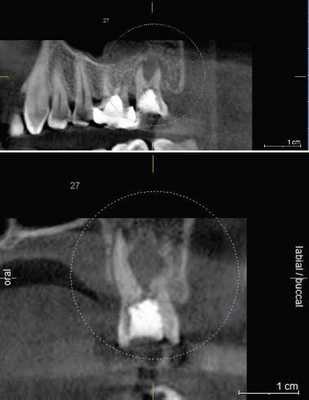

Первая - легкая степень обусловливалась сдавлением ствола за счет отека, гематомы или прямой, непосредственной, но незначительной компрессией имплантатом. Рентгенологическое исследование посредством конусно-лучевой компьютерной томографии и программного обеспечения Ez3D-iV4.3.0 от Vatech, при маркировке нижнечелюстного канала, установило расположение дентальных имплантатов непосредственно у нижнечелюстного канала или эндопротезы перфорировали верхнюю стенку канала (Рис.2). Тактика лечения такого вида патологии основывается на сохранении имплантатов, назначении витаминов группы В, средств, оказывающих непосредственное стимулирующее влияние на проведение импульса по нервным волокнам, усиливающих сократимость гладкомышечной мускулатуры под влиянием агонистов ацетилхолиновых, адреналиновых, серотониновых, гистаминовых и окситоциновых рецепторов. Нарушение чувствительности во всех наблюдениях этой группы носило временный характер и восстановилось через 4-6 недель.

Рис.2 Конусно-лучевая компьютерная томография от Vatech. Нижнечелюстной канал маркирован с помощью программного обеспечения Ez3D-iV4.3.0.

Результаты рентгенологического исследования показали, что дентальная объемная томография наиболее информативный метод при оценке степени повреждения нижнего альвеолярного нерва. Истинное трехмерное изображение исследуемого объекта и вращение его вокруг любой из трех осей на 360 градусов, позволяют визуализировались положение имплантата по отношению к нижнечелюстному каналу и документировать степень его повреждения. Программное обеспечение Ez3D-iV4.3.0 от Vatech предполагает огромный функциональный набор. Применительно к диагностике повреждения нерва после имплантации в данном софте в режиме высокого качества разрешения возможна трехпроекционная реконструкция, с возможностями переориентации осей, с измерением габаритов объекта исследования в масштабе 1:1(рис.3).

Рис.3 Конусно-лучевая компьютерная томография от Vatech. На коронарной проекции определяется верхушка дентального имплантата 3.6, перфорирующая медиальную стенку нижнечелюстного канала.